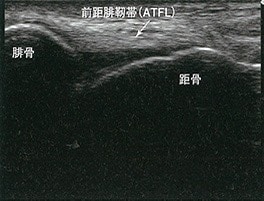

次に足首のエコー画像

このように写る範囲は広くありませんが、骨に限らず軟部組織も捉えられるのが特徴です。